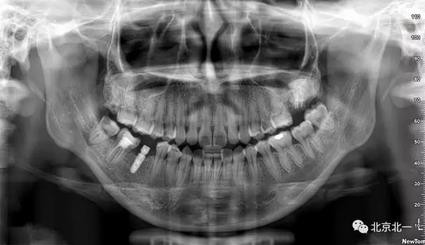

患者 成年女性,上頜反復(fù)腫痛不適,檢查發(fā)現(xiàn)27殘根, 拍全景片發(fā)現(xiàn)埋伏智齒, 建議27、28拔除。

圖二:全景片見(jiàn)27區(qū)高密度影像,考慮智齒埋伏,拍CBCT確認(rèn)。